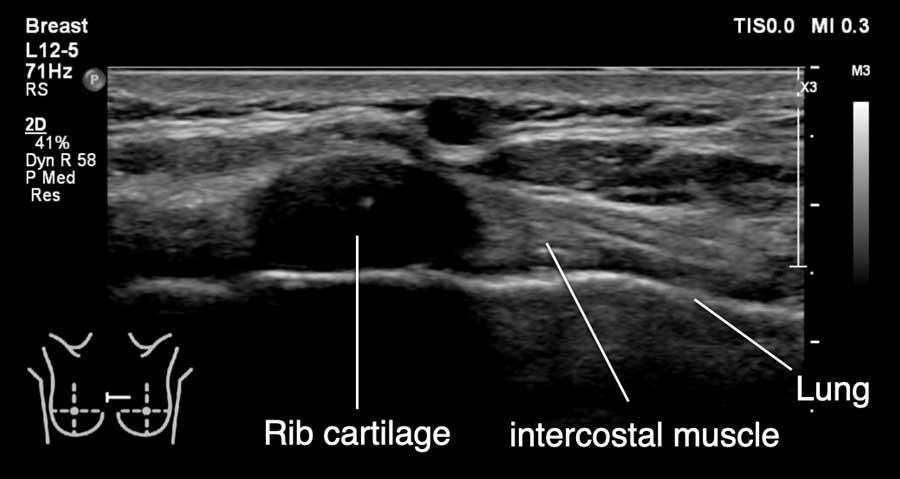

Gần đường giữa, các xương sườn chỉ được cấu tạo bởi sụn và chưa bị vôi hóa.

Sụn không tạo ra phản âm trắng ở mặt trước hay bóng cản âm phía sau.

Thay vào đó, một cấu trúc giảm âm được quan sát thấy phía trước phổi.

Không nên nhầm lẫn cấu trúc này với khối u vú.

Thoạt nhìn, cấu trúc này có thể trông giống u xơ tuyến vú khi hình ảnh xương sườn được cắt trên mặt phẳng ngang.

Khi xoay đầu dò, sẽ nhận thấy đây là một cấu trúc dài liên tục với phần xương sườn đã vôi hóa.

Video này minh họa hình ảnh sụn xương sườn bình thường.

Bằng cách xoay đầu dò, có thể thấy xương sườn là một cấu trúc chạy dọc, nằm phía trước phổi và phía sau cơ ngực.